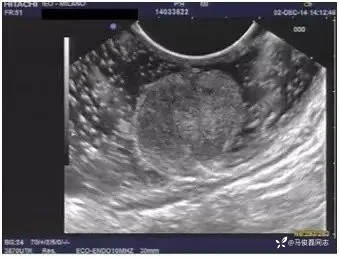

6、诊断直肠神经内分泌瘤,需要做超声内镜么?

答:直径超过1cm的直肠神经内分泌瘤需要超声内镜检查明确侵犯深度和排除肠周淋巴结转移,1cm以内的可以不做。